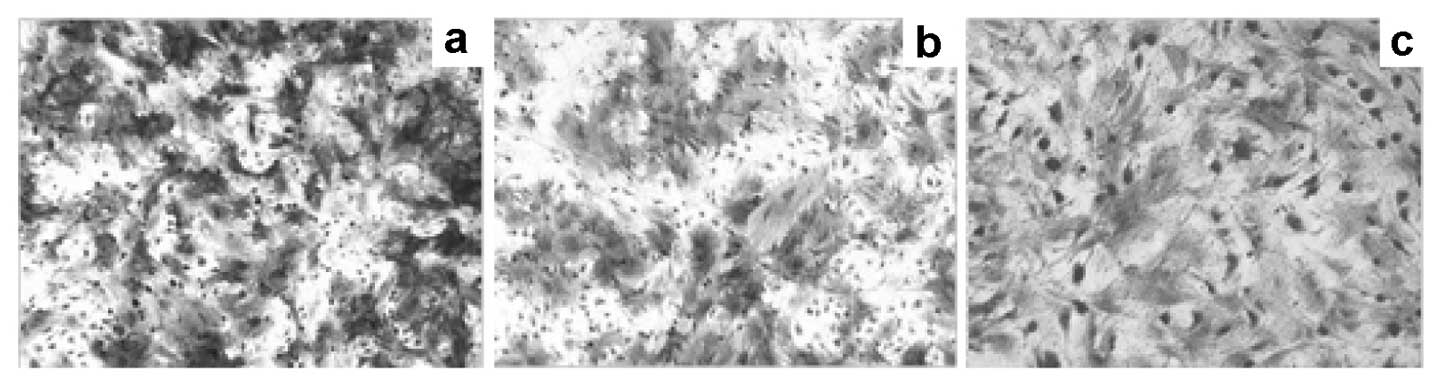

Prostate cancer (PCa) is the most common type of cancer worldwide. Mesenchymal stem cells (MSCs) can also be utilized as ‘tumor stromal cells’, which are associated with invasive and metastatic malignant tumor cells. Our study aimed to investigate MSCs in prostate tumors and normal MSCs and evaluate their differential characteristics. Normal MSCs (BMMSCs) were isolated from the femur and tibia of normal mice; prostate tumor MSCs (PCa-MSCs) were obtained from prostate tumors implanted in mice. These two types of MSCs were induced to differentiate into adipocytes, bone cells and chondrocytes. Growth curves were used to analyze the growth ability of PCa-MSCs and BMMSCs. Tritium-labeled thymidine (3H-TdR) was used to evaluate cell proliferation of RM-1 stimulated by MSCs. The time taken for PCa-MSCs to reach 90% confluence was markedly shorter than that of BMMSCs (8-10 vs. 12-14 days). The differentiation ability of PCa-MSCs was similar to that described in previous reports. The growth ability of PCa-MSCs was significantly higher than that of BMMSCs. The proliferative activity of PCa-MSCs was also higher than that of BMMSCs. Our data showed that PCa-MSCs exhibit identical characteristics when compared with those of MSCs. Additionally, their proliferative activity and growth ability were significantly higher when compared with these values in BMMSCs, which appear to have an intrinsic, cell-specific capacity to localize to PCa. The possible role of PCa-MSCs in the process of PCa development requires further clarification.

Figure 2